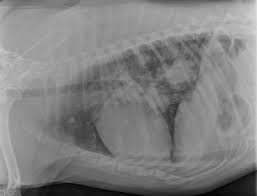

In the beginning stages, many dogs show no clinical signs. Pulmonary adenocarcinoma is cancer of the lungs, which can be primary (originates in the lungs) or secondary (originates somewhere else in the body), is a serious disease that can be fatal if not found and treated early. Metastic neoplasia (cancer) in dogs. That said, here are some general signs and symptoms that indicate the possibility of lung cancer: Almost 70% of dogs with lung cancer experience metastasis to other parts of the lung, meaning treatment may only prolong their life rather than eliminating the disease completely. However, some dogs only experience weight loss (despite a good appetite) and/or lack of energy. Metastatic lung tumors are tumors originating from a cancer elsewhere in the body which has spread to the pet's lungs. Symptoms of lung cancer in dogs usually there are no symptoms in the early stages of canine lung cancer. As the cancer grows, dogs may develop a cough, difficulty breathing, and other symptoms. Lung tumors are relatively rare in dogs, accounting for only 1% of all cancers diagnosed. Life expectancy of a dog with lung cancer. The protocol will often differ based on the symptoms your dog presents with. Computed tomography (ct scan) can be performed to identify some of these lung tumors.

Life Expectancy Of Dog With Metastatic Lung Cancer from media.springernature.com It is estimated that 25% of dogs with a lung tumor show no related signs of cancer. Computed tomography (ct scan) can be performed to identify some of these lung tumors. The dog is not coughing up mucus) although the cough may produce small amounts of phlegm or blood. We have been using prednisone to help with the breathing from the lung tumor, also turkey tail mushroom for the heart tumor, we are also using cbd oil, and just recently added apocaps. Some of the most common ways to test for cancer in dogs include: Symptoms of lung cancer in dogs. Pulmonary adenocarcinoma is cancer of the lungs, which can be primary (originates in the lungs) or secondary (originates somewhere else in the body), is a serious disease that can be fatal if not found and treated early. The second type is metastatic lung cancer whichis cancer that originates elsewhere in the body such as a leg bone, the mouth, or the thyroid gland, but has spread to the lung via the bloodstream.

When it comes to diagnosing cancer in dogs, there are a number of ways to go about this. However, some dogs only experience weight loss (despite a good appetite) and/or lack of energy. Melanomas in dogs tend to affect the mouth and lips, and they can also be found on their nail beds, footpads and eyes. Symptoms of lung cancer in dogs. Lung tumors have moderate to high potential for metastasis (spreading). Life expectancy of a dog with lung cancer. When they do cough, they might bring up blood. Lung tumors are relatively rare in dogs, accounting for only 1% of all cancers diagnosed. The dog may cough up blood, but not mucus. Anonymous we are going through a similar issue. However, some dogs only experience weight loss (despite a good appetite) and/or lack of energy. Lung cancer in pets is rare. Lung cancer in dogs symptoms the symptoms of lung cancer are coughing (which may produce phlegm or blood), exercise intolerance (lethargy), loss of weight or loss of appetite and other respiratory symptoms such as difficulty breathing or shortness of breath.

In general, symptoms develop based on where the metastatic cancer is located, how invasive it is and how long it has been present. In the absence of diagnostic testing, it can be challenging to detect lung cancer in dogs. Cancer of the lungs is a progressive disease, meaning it gets worse over time. That said, here are some general signs and symptoms that indicate the possibility of lung cancer: The dog may cough up blood, but not mucus. At this stage, the tumor can be removed through surgery. The symptoms of metastatic cancer in dogs are not universal. Chronic coughing seems to be the most common abnormality that is seen in dogs with lung cancer. Adenocarcinoma of the lung in dogs. Unlike some other types of cancer, there are some concerning symptoms that arise in the earlier stages of primary lung cancer for dogs that should immediately alert you that something is wrong. Lung cancer in dogs symptoms the symptoms of lung cancer are coughing (which may produce phlegm or blood), exercise intolerance (lethargy), loss of weight or loss of appetite and other respiratory symptoms such as difficulty breathing or shortness of breath. On top of dogs presenting symptoms derived from the primary tumor, in advanced cases, dogs will also show signs of lung cancer. Symptoms of lung metastases pulmonary metastases may not produce symptoms.